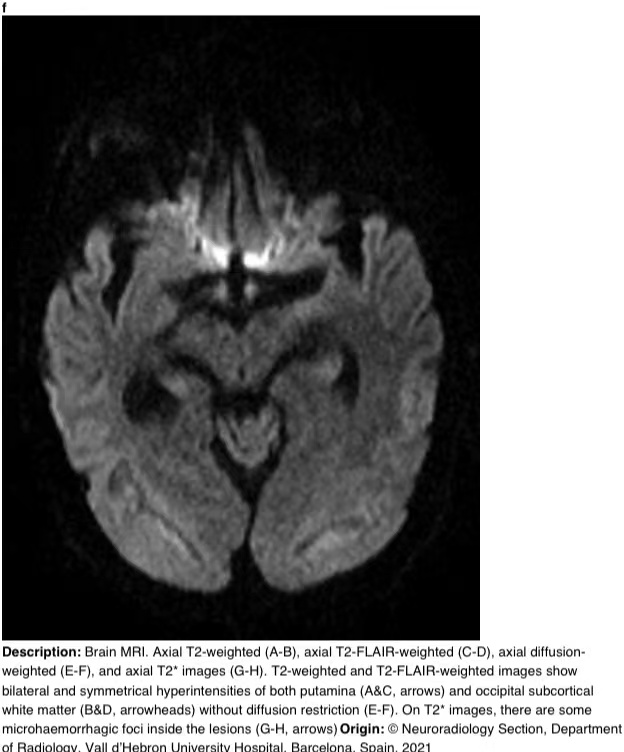

在16天的随访中,脑部MRI显示壳核和枕下皮质下白质上对称的T2/FLAIR高信号。T2图像显示病变内有微出血(图3)。

图3f

图3 a-h 脑部核磁共振成像。轴向T2加权(A-B)、轴向T2 FLAIR加权(C-D)、轴向弥散加权(E-F)和轴向T2图像(G-H)。T2加权和T2 FLAIR加权图像显示双侧和对称的壳核高信号(A和C,箭头)和枕下皮质下白质高信号(B和D,箭头),无弥散限制(E-F)。在T2图像上,病变内有一些微出血病灶(G-H,箭头)。